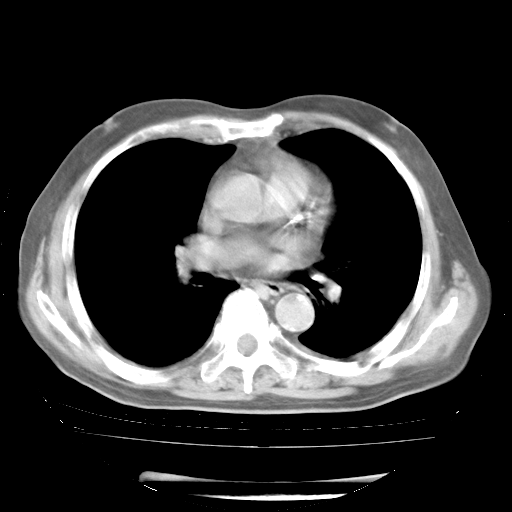

4月28日肺部CT

1、108#的是4月14日的胸部CT(发此贴时还没看着28日的CT)。14日的胸部CT其实已经出现改变(如108#所述),个人认为28日的胸部CT除纵膈窗疑似有双侧胸膜增厚或少量胸积液(可行胸部B超明确)外,与4月14日对照病变有所加重;2、已经给予“异烟肼、利福平、乙胺丁醇”抗痨治疗?如果是,甲强龙80mg可缓慢减量;如果环磷酰胺已停用,暂不使用;3、中性粒细胞92%,明显升高,目前体温情况?注意合并细菌感染可能,使用左氧氟沙星情况下,是否联用B-内酰胺类抗菌药物?另外是查免疫全套非风湿全套。

今请临免主任会诊后认为:4月14日胸部CT已有双下肺间质性改变。患者病情复发多系激素减量过快不正规所致。目前甲强龙80mg/日,一周后酌情开始减量,不易过快。环磷酰胺若已停用,暂不使用。他同意目前抗菌药物使用,但应考虑是否加用B-内酰胺类抗菌药物(中性细胞明显增高);2、结核复发目前依据不足;3、若免疫全套各项指标正常,考虑多系特发性肺间质炎可能大。4、加强支持,并注意保护胃黏膜。

今上午去请教了临免、呼吸主任:1、介绍病史和阅读系列胸部CT一致认为:患者肺结核不考虑,仍为肺间质纤维化,目前处于急性肺泡炎阶段。2、若仍发热,可将甲强龙增至:80mg Bid静滴,同时鉴于中性增高,合并细菌感染可能,继续左氧氟沙星治疗,再联用B-内酰胺抗菌药物,如头孢哌酮--舒巴坦;3、停用抗痨药;4、目前甲强龙每日剂量160mg ,体温正常后再酌情减量;目前暂不用免疫抑制剂;4、不建议使用免疫增强剂等;5、加强支持治疗,鼓励患者进食;5、注意随访肝、肾功及血常规情况;6、因患者目前激素用量较大,加用胃黏膜保护剂,防止消化道出血可能。